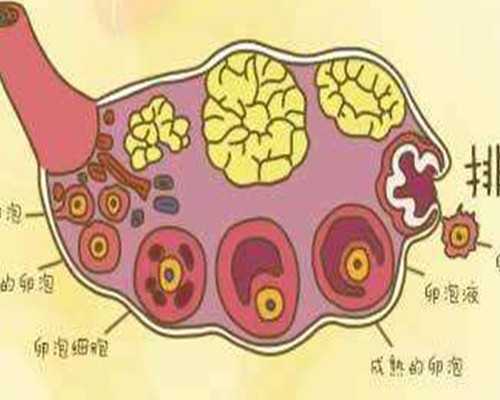

2.雌二醇很低到底有沒有關系,試管嬰兒,移植后

1)雌二醇偏低最直接的危害是導致女性不孕,因為它主要激發卵泡發育,同時血清雌二醇水平也間接上影響了卵巢功能,偏低則導致不排卵,影響生育;(2)女性的子宮、外陰、生殖道等器官的發育需要各類雌激素,如果雌二醇等激素水平降低則最終導致,女性子宮、外陰、生殖道萎縮;(3)雌二醇過低還會造成女性子宮內膜變薄,最終影響到月經量,直接影響到卵泡發育誘發不孕癥,除此外雌二醇偏低還會造成身體上出現一些更年期癥狀,如情緒不穩、失眠、潮熱、出汗等。盡早治療對于雌二醇增高有很好的調理作用,一般可通過一些雄激素類藥物來促使雌二醇恢復到正常水平。在做試管嬰兒之前醫生會根據患者的具體報告來進行診斷,是否能夠進行試管也需要根據患者自身的水平進行考慮。

5.雌二醇很低到底有沒有關系,試管嬰兒,移植后

1)雌二醇偏低最直接的危害是導致女性不孕,因為它主要激發卵泡發育,同時血清雌二醇水平也間接上影響了卵巢功能,偏低則導致不排卵,影響生育;(2)女性的子宮、外陰、生殖道等器官的發育需要各類雌激素,如果雌二醇等激素水平降低則最終導致,女性子宮、外陰、生殖道萎縮;(3)雌二醇過低還會造成女性子宮內膜變薄,最終影響到月經量,直接影響到卵泡發育誘發不孕癥,除此外雌二醇偏低還會造成身體上出現一些更年期癥狀,如情緒不穩、失眠、潮熱、出汗等。盡早治療對于雌二醇增高有很好的調理作用,一般可通過一些雄激素類藥物來促使雌二醇恢復到正常水平。在做試管嬰兒之前醫生會根據患者的具體報告來進行診斷,是否能夠進行試管也需要根據患者自身的水平進行考慮。

6.雌二醇很低到底有沒有關系,試管嬰兒,移植后

1)雌二醇偏低最直接的危害是導致女性不孕,因為它主要激發卵泡發育,同時血清雌二醇水平也間接上影響了卵巢功能,偏低則導致不排卵,影響生育;(2)女性的子宮、外陰、生殖道等器官的發育需要各類雌激素,如果雌二醇等激素水平降低則最終導致,女性子宮、外陰、生殖道萎縮;(3)雌二醇過低還會造成女性子宮內膜變薄,最終影響到月經量,直接影響到卵泡發育誘發不孕癥,除此外雌二醇偏低還會造成身體上出現一些更年期癥狀,如情緒不穩、失眠、潮熱、出汗等。盡早治療對于雌二醇增高有很好的調理作用,一般可通過一些雄激素類藥物來促使雌二醇恢復到正常水平。在做試管嬰兒之前醫生會根據患者的具體報告來進行診斷,是否能夠進行試管也需要根據患者自身的水平進行考慮。

3.雌二醇很低到底有沒有關系,試管嬰兒,移植后

1)雌二醇偏低最直接的危害是導致女性不孕,因為它主要激發卵泡發育,同時血清雌二醇水平也間接上影響了卵巢功能,偏低則導致不排卵,影響生育;(2)女性的子宮、外陰、生殖道等器官的發育需要各類雌激素,如果雌二醇等激素水平降低則最終導致,女性子宮、外陰、生殖道萎縮;(3)雌二醇過低還會造成女性子宮內膜變薄,最終影響到月經量,直接影響到卵泡發育誘發不孕癥,除此外雌二醇偏低還會造成身體上出現一些更年期癥狀,如情緒不穩、失眠、潮熱、出汗等。盡早治療對于雌二醇增高有很好的調理作用,一般可通過一些雄激素類藥物來促使雌二醇恢復到正常水平。在做試管嬰兒之前醫生會根據患者的具體報告來進行診斷,是否能夠進行試管也需要根據患者自身的水平進行考慮。

5.雌二醇很低到底有沒有關系,試管嬰兒,移植后

1)雌二醇偏低最直接的危害是導致女性不孕,因為它主要激發卵泡發育,同時血清雌二醇水平也間接上影響了卵巢功能,偏低則導致不排卵,影響生育;(2)女性的子宮、外陰、生殖道等器官的發育需要各類雌激素,如果雌二醇等激素水平降低則最終導致,女性子宮、外陰、生殖道萎縮;(3)雌二醇過低還會造成女性子宮內膜變薄,最終影響到月經量,直接影響到卵泡發育誘發不孕癥,除此外雌二醇偏低還會造成身體上出現一些更年期癥狀,如情緒不穩、失眠、潮熱、出汗等。盡早治療對于雌二醇增高有很好的調理作用,一般可通過一些雄激素類藥物來促使雌二醇恢復到正常水平。在做試管嬰兒之前醫生會根據患者的具體報告來進行診斷,是否能夠進行試管也需要根據患者自身的水平進行考慮。

6.雌二醇很低到底有沒有關系,試管嬰兒,移植后

1)雌二醇偏低最直接的危害是導致女性不孕,因為它主要激發卵泡發育,同時血清雌二醇水平也間接上影響了卵巢功能,偏低則導致不排卵,影響生育;(2)女性的子宮、外陰、生殖道等器官的發育需要各類雌激素,如果雌二醇等激素水平降低則最終導致,女性子宮、外陰、生殖道萎縮;(3)雌二醇過低還會造成女性子宮內膜變薄,最終影響到月經量,直接影響到卵泡發育誘發不孕癥,除此外雌二醇偏低還會造成身體上出現一些更年期癥狀,如情緒不穩、失眠、潮熱、出汗等。盡早治療對于雌二醇增高有很好的調理作用,一般可通過一些雄激素類藥物來促使雌二醇恢復到正常水平。在做試管嬰兒之前醫生會根據患者的具體報告來進行診斷,是否能夠進行試管也需要根據患者自身的水平進行考慮。

8.雌二醇很低到底有沒有關系,試管嬰兒,移植后

1)雌二醇偏低最直接的危害是導致女性不孕,因為它主要激發卵泡發育,同時血清雌二醇水平也間接上影響了卵巢功能,偏低則導致不排卵,影響生育;(2)女性的子宮、外陰、生殖道等器官的發育需要各類雌激素,如果雌二醇等激素水平降低則最終導致,女性子宮、外陰、生殖道萎縮;(3)雌二醇過低還會造成女性子宮內膜變薄,最終影響到月經量,直接影響到卵泡發育誘發不孕癥,除此外雌二醇偏低還會造成身體上出現一些更年期癥狀,如情緒不穩、失眠、潮熱、出汗等。盡早治療對于雌二醇增高有很好的調理作用,一般可通過一些雄激素類藥物來促使雌二醇恢復到正常水平。在做試管嬰兒之前醫生會根據患者的具體報告來進行診斷,是否能夠進行試管也需要根據患者自身的水平進行考慮。

10.雌二醇很低到底有沒有關系,試管嬰兒,移植后

1)雌二醇偏低最直接的危害是導致女性不孕,因為它主要激發卵泡發育,同時血清雌二醇水平也間接上影響了卵巢功能,偏低則導致不排卵,影響生育;(2)女性的子宮、外陰、生殖道等器官的發育需要各類雌激素,如果雌二醇等激素水平降低則最終導致,女性子宮、外陰、生殖道萎縮;(3)雌二醇過低還會造成女性子宮內膜變薄,最終影響到月經量,直接影響到卵泡發育誘發不孕癥,除此外雌二醇偏低還會造成身體上出現一些更年期癥狀,如情緒不穩、失眠、潮熱、出汗等。盡早治療對于雌二醇增高有很好的調理作用,一般可通過一些雄激素類藥物來促使雌二醇恢復到正常水平。在做試管嬰兒之前醫生會根據患者的具體報告來進行診斷,是否能夠進行試管也需要根據患者自身的水平進行考慮。